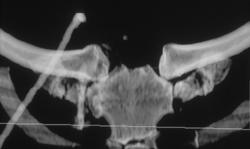

Acetabular Fracture